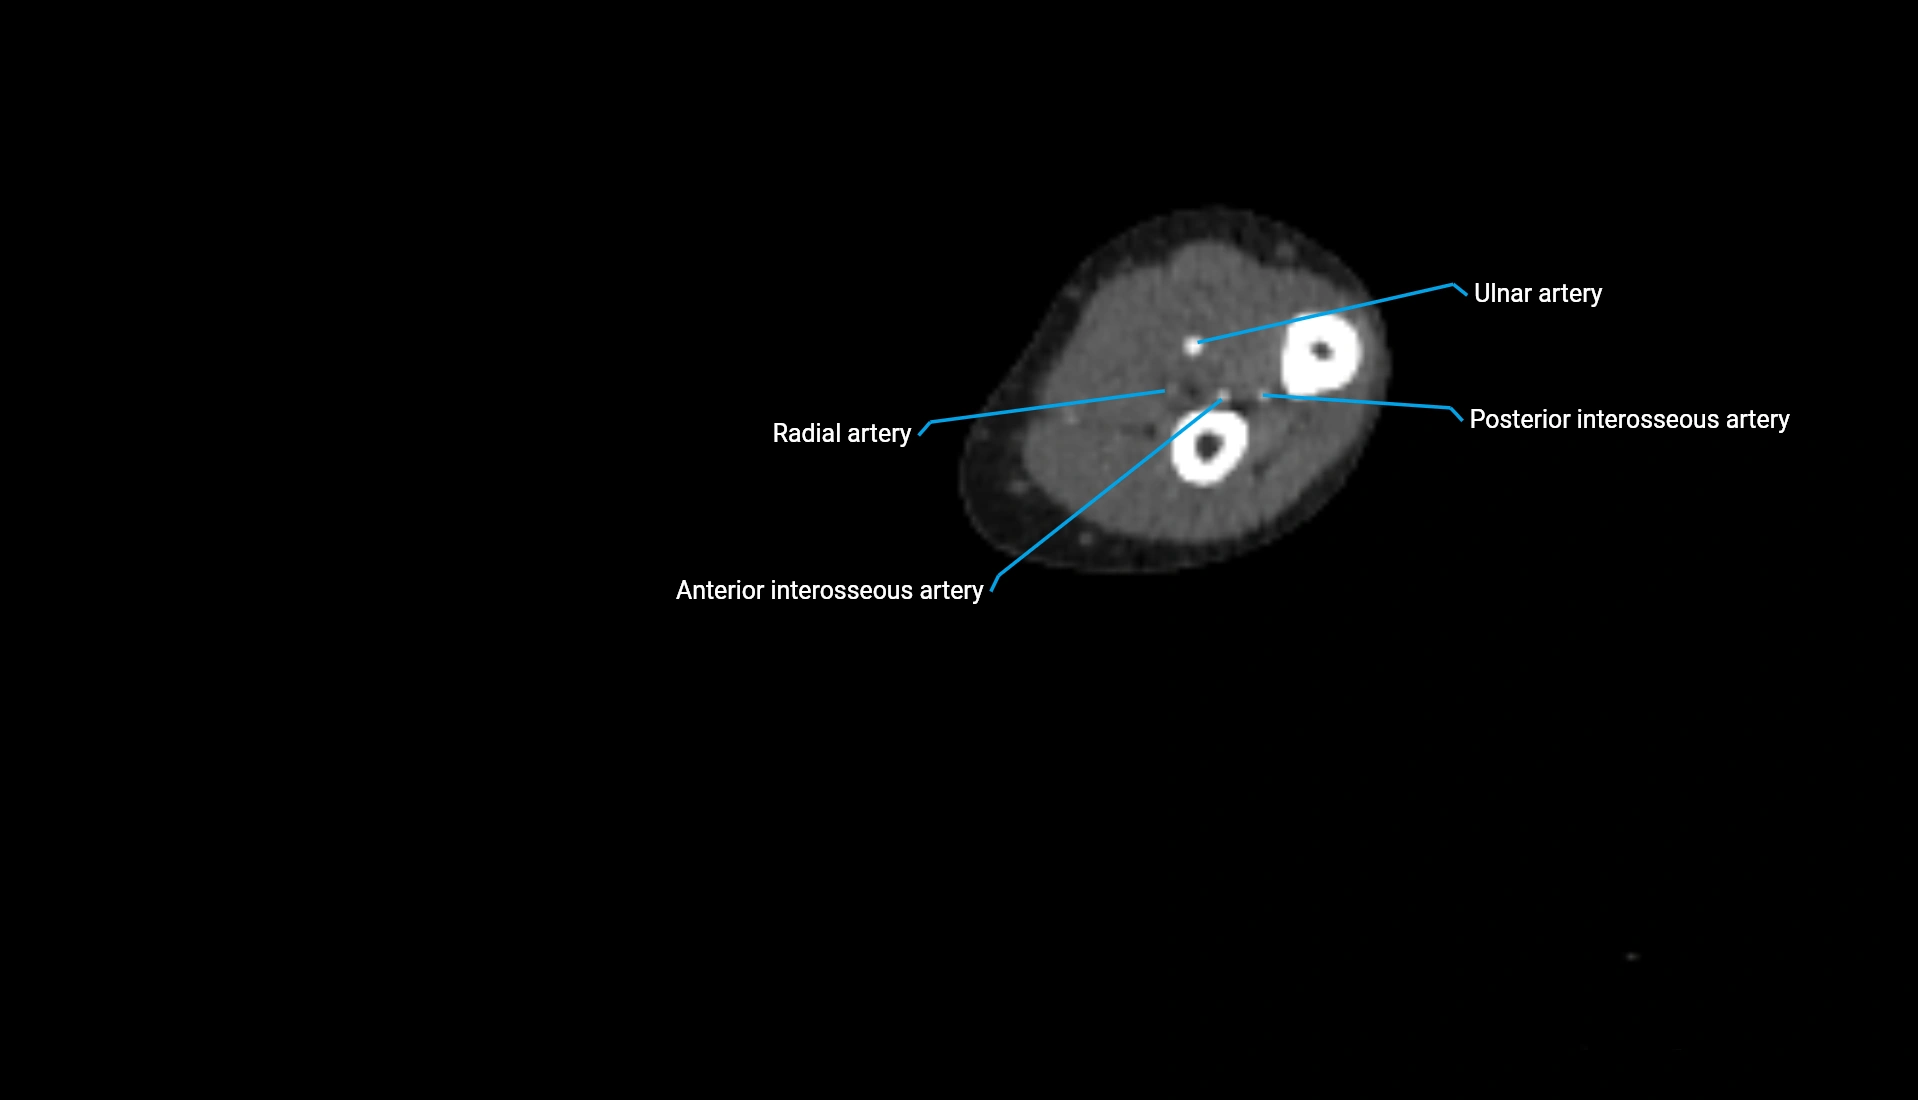

CT Appearance

Non-Contrast CT:

• Cortex: High-density, sharply defined

• Subchondral bone: Dense cancellous matrix

• Articular surface: Smooth concave contour articulating with the capitellum

• Excellent for evaluating bone integrity, alignment, and subtle fractures